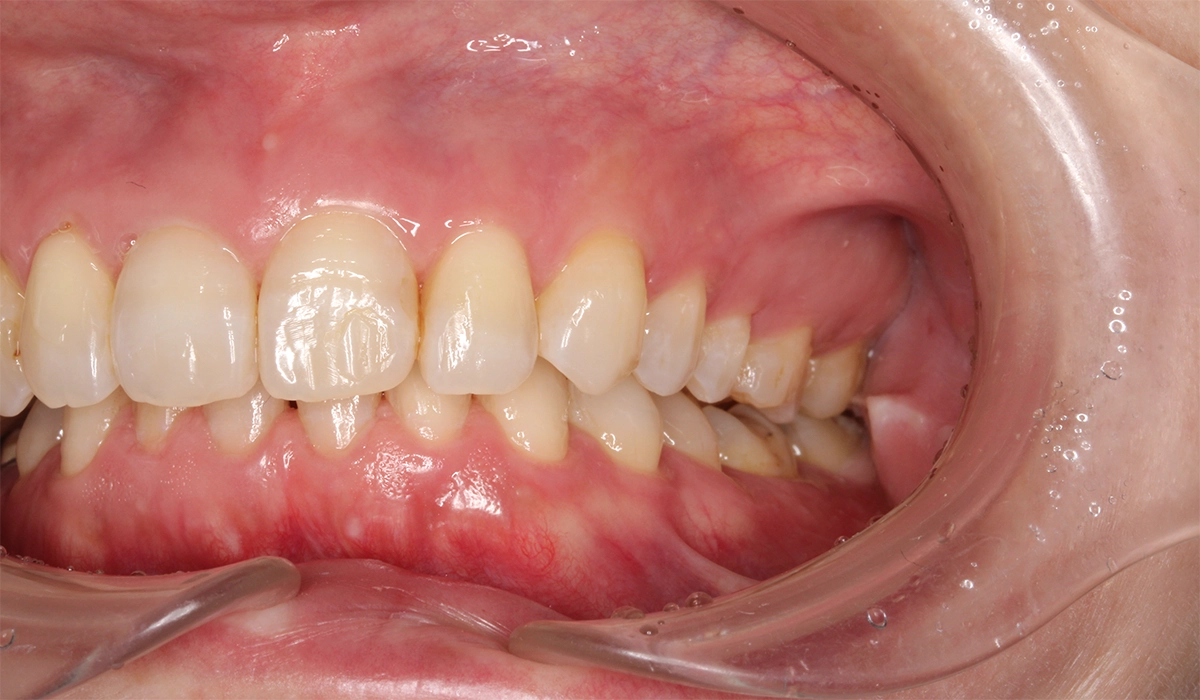

術前:右側